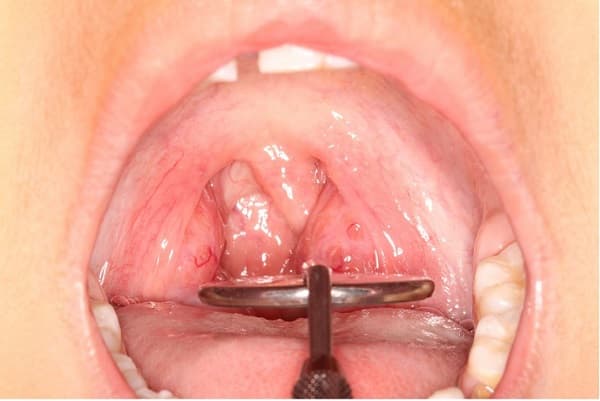

Triệu chứng ung thư vòm họng tái phát

Ung thư vòm họng sau khi điều trị vẫn có một tỉ lệ nhỏ tái phát. Tại sao lại có tình trạng này và triệu chứng ung thư vòm họng tái phát thế nào là vấn đề được đông đảo bệnh nhân và người nhà quan tâm. 1. Tại sao ung thư vòm họng tái […]